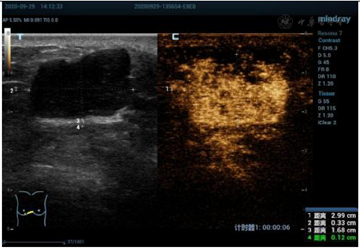

乳腺超声显示(图1):右侧乳腺5点半距乳头8~10 cm腺体边缘近胸骨旁扫见混合回声结节,大小约26 mm×15 mm,距体表6 mm,边界清晰,形态欠规则,内部回声欠均匀,后方回声略增强,CDFI:可见少许血流信号(图2)。弹性成像显示肿块硬度尚可(图3)诊断为BI-RADS 4a类,建议行乳腺超声造影。行超声造影后提示:增强早期肿块与周围乳腺组织相比,造影剂呈向心性、快进、高增强(图4),分布均匀,周边未见明显滋养血管,造影后范围30 mm×17 mm,大于二维超声;增强晚期造影剂缓慢消退,诊断为BI-RADS 4c类。